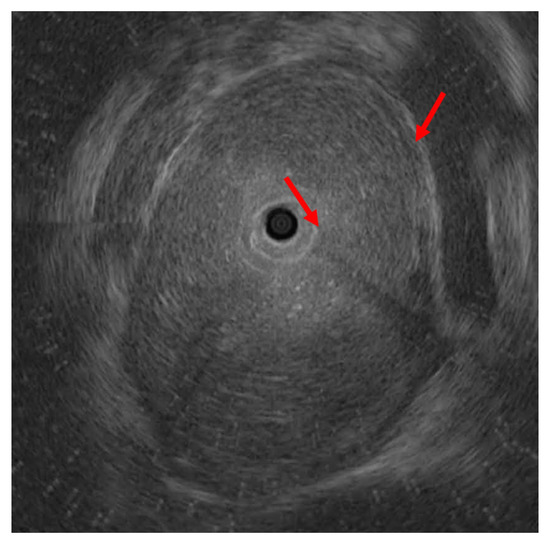

2. Detailed Case Description